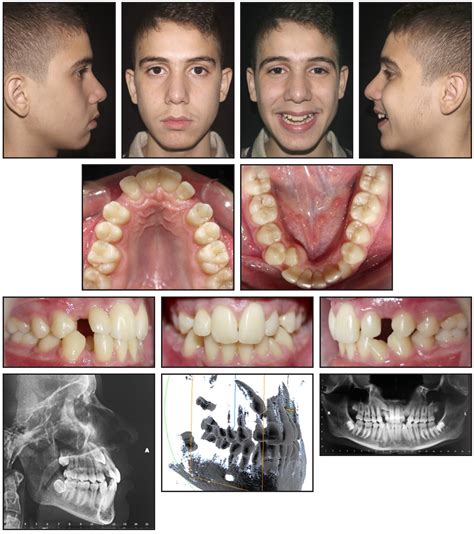

IMPACTED CANINE EXTRACTION COMPLICATION: CASE.